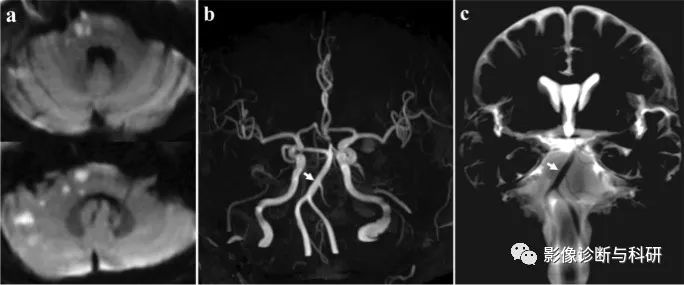

弥散加权图像显示左小脑前下动脉 (AICA) 区域梗死 ( a )。在磁共振血管造影中,左侧 AICA 缺失,而右侧 AICA 清晰可见 ( b )。基础平行解剖扫描磁共振成像(BPAS MRI)显示双侧 AICA 正常(c)